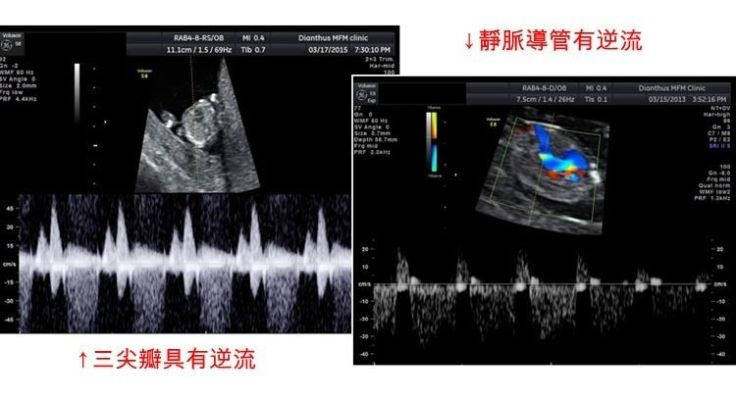

於早期的相關研究中,發現頸部透明帶的增厚與唐氏症,及其他許多染色體異常有高度相關,在後續的研究中,陸續加入的生化指標、以及靜脈導管逆流、三尖瓣逆流、以及鼻骨有無等等軟指標,讓系統的檢出率一路從80%左右提升到93%以上。而且,過程中的不斷發展,近年又加上了可以同時進行子癲前症的篩檢,以及早產評估 。當然,幾近99.5%以上準確率之非侵入性染色體篩檢(NIPS)的發展,則又是另一件事了(這題目請容後再談..)。

如果接受這項檢查,務必要搞清楚自己做的項目內容,以及所擁有的檢測率是很重要的,因為,這牽扯到您個人的風險管理。譬如說,有些院所只測量頸部透明帶加上抽血生化二指標。不做其他的軟指標,則檢測率只有80%,而不是加上靜脈導管逆流、三尖瓣逆流、以及鼻骨有無等等,全部標準量測的93%檢出率,這點,還是一定要搞清楚。